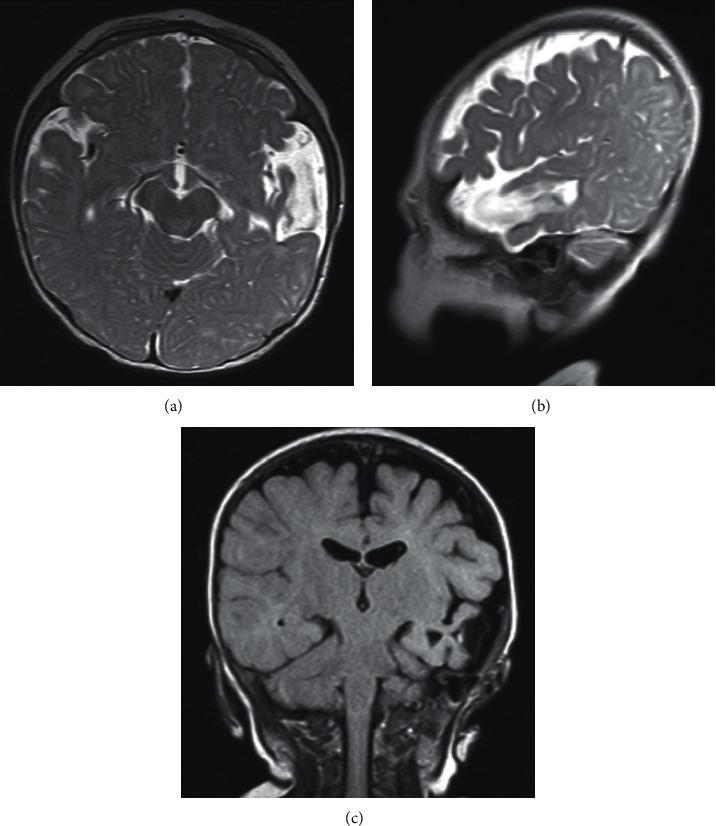

. Congenital toxoplasmosis is a major sequela of untreated primary maternal infection. With or without symptoms, untreated infections eventually lead to multiple neurologic complications. Despite the high seroprevalence in the Ethiopian population, there are no reports of newborns diagnosed and treated for congenital toxoplasmosis. . The clinical presentation, evaluation, and management of three infants with congenital toxoplasmosis are described. Two were symptomatic at birth. All three had confirmed diagnoses using serologic tests. Two completed their treatment with one infant developing complications of strabismus and seizure disorder. . There is little experience in managing congenital toxoplasmosis in Ethiopia due to constraints in diagnostics and therapy. The description of this first such report underscores the need for risk assessment and evaluation during antenatal care to obtain favorable fetal outcomes.

先天性弓形虫病是未治疗的原发性母体感染的主要后遗症。无论有无症状,未治疗的感染最终都会导致多种神经系统并发症。尽管埃塞俄比亚人群中血清阳性率很高,但尚无关于先天性弓形虫病新生儿诊断和治疗的报告。本文描述了3例先天性弓形虫病婴儿的临床表现、评估和管理。2例出生时出现症状。所有3例均通过血清学检测确诊。2例完成了治疗,其中1例出现斜视和癫痫障碍并发症。由于诊断和治疗方面的限制,埃塞俄比亚在管理先天性弓形虫病方面经验很少。这第一份此类报告的描述强调了在产前护理期间进行风险评估和评估以获得良好胎儿结局的必要性。